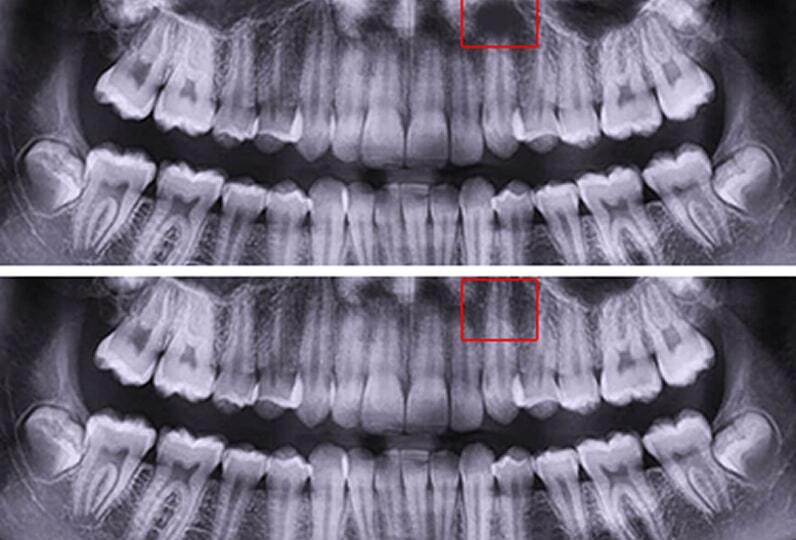

Гайморит, деструкция костной ткани в области верхушек корней зубов